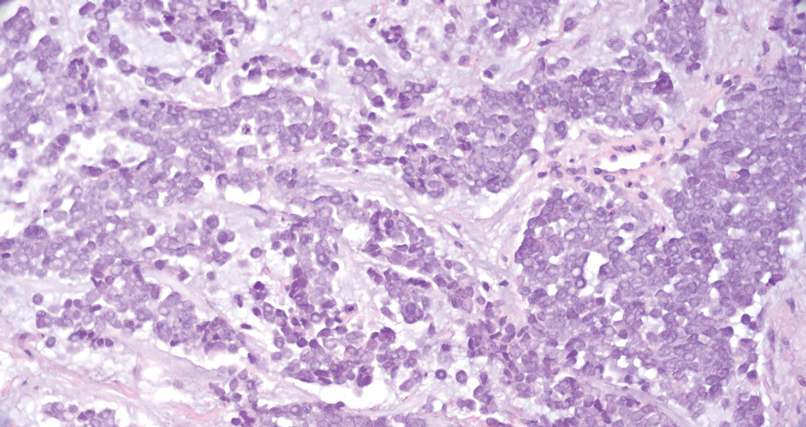

Squamoid eccrine ductal carcinoma is a rare primary cutaneous tumor with aggressive features that can be confused both clinically and histologically with squamous cell carcinoma (SCC). Histologically, SEDC is a biphasic tumor. If a shallow histologic specimen is obtained, it may be indistinguishable from a well-differentiated SCC (Figure 1). A deeper biopsy reveals irregular infiltrative cords and strands exhibiting ductal differentiation in a fibrotic stroma.1